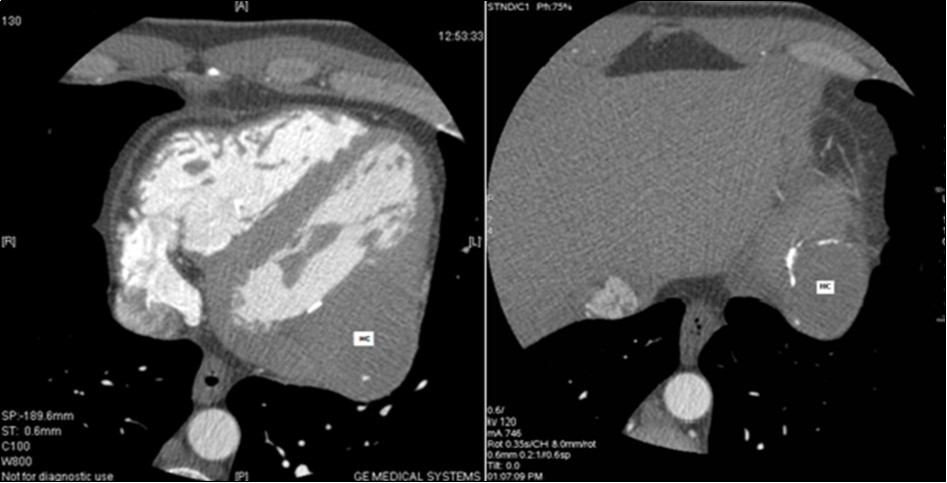

The 64-slice computed tomography (CT) showed a left ventricle intra-myocardial mass of tissue density (25 HU), not enhancing after injection of contrast, and containing multiple central and peripheral arciform calcifications (Figure 3,Figure 4,and Figure 5).

Figure 4.Coroscanner: left ventricle intra-myocardial mass of parenchymal density and calcified wall (HC: hydatid cyst).

Figure 5.Coroscanner with three-dimensional reconstruction: intra-myocardial mass of left ventricle with multiple calcifications.

After these explorations, the radiological aspect was very suggestive of a cardiac HC type V of the Gharbi classification. The hydatid serology was negative. The assessment for other hydatid locations (chest X-ray, abdominal ultrasound, and thoraco-abdomino-pelvic CT) remained negative.